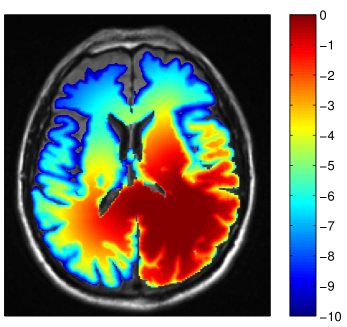

Refer to caption

(a) cell density

(b) model-derived target

(c) manual target

(d) dose difference

Figure 9: (a) Simulated tumor cell density for the patient shown in figure 8; (b-c) Comparison of IMRT dose distributions (in units of Gy) of the plan based on manual target volume (c) and the model-derived target volume (b). The difference of the dose distributions is shown in (d).

Figure 8 shows a multifocal GBM case involving the left temporal lobe as well as the frontal lobe. Figure 8a shows the coronal T1 post contrast image, revealing the contrast enhancing tumor mass in the temporal lobe. The axial T1 post contrast image in figure 8b shows the lesion in the frontal lobe. The simulated tumor cell density in figure 9a illustrates several features discussed in sections 3 and 4: The tumor growth model describes the steep fall-off of the tumor cell density in gray matter, leading to differences in the target volume around the lateral sulcus (figure 8b). In addition, modeling tumor cell infiltration through the corpus callosum leads to differences in the target volume in the contralateral frontal lobe. Figure 9 shows the IMRT plan comparison for a homogeneous 60 Gy prescription to the manual CTV (c) and the model-derived CTV (b). The figure shows that the differences in the target volume partly translate into differences in the dose distribution. In particular, the dose difference plot in figure 9d shows a lower dose in the lateral sulcus region for the model-based plan, and a higher dose in the contralateral hemisphere close to the corpus callosum.